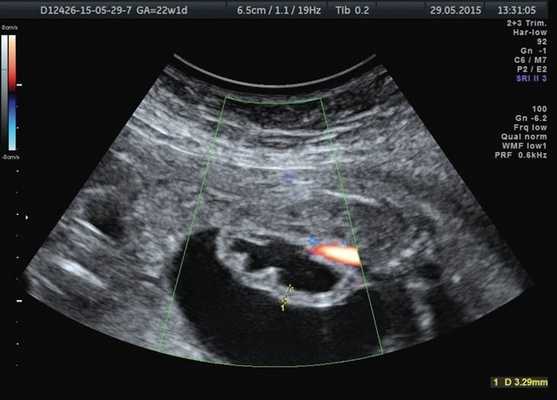

Лоханка правой почки была расширена до 13 мм, паренхима истончена и гиперэхогенна, кортикомедуллярная дифференцировка отсутствовала. При ЦДК кровоток в паренхиме не визуализировался. Вокруг правой почки по всему ее периметру определялось анэхогенное образование размером 56×20×26 мм (рис. 1, 2). Мочеточники с обеих сторон не визуализировались. Изменения левой почки отсутствовали. Мочевой пузырь был удовлетворительного наполнения и опорожнения. Оба надпочечника визуализировались.

Рис. 2. Истончение паренхимы правой почки плода с отсутствием кровотока в режиме ЦДК.